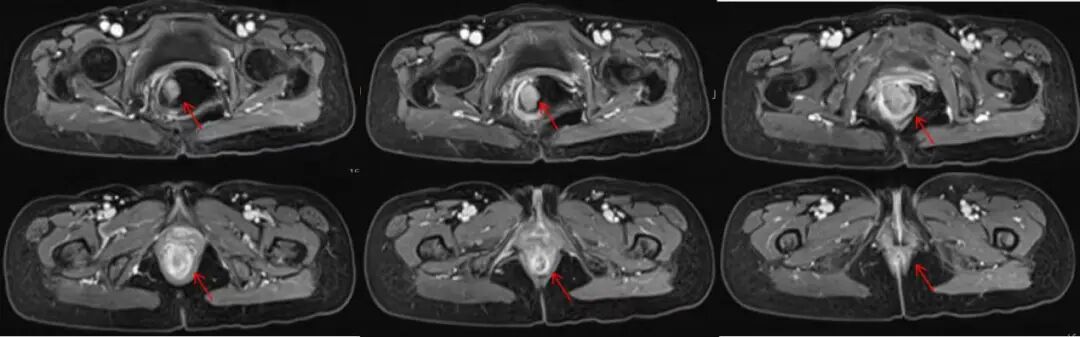

图注:盆腔MRI可见直肠腔内及肛缘附近软组织肿物,病灶明显强化;肿物根部位于肛缘旁,凸向直肠内,造成肠内积气。